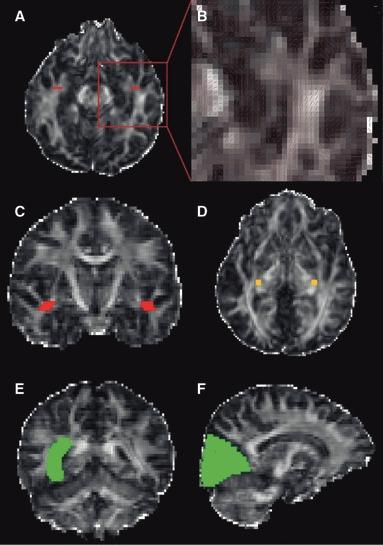

About one-third of patients with epilepsy are refractory to medical treatment and may be amenable to surgery. However, in patients with lesions on or near the presumed course of the optic radiation, the potential benefits of resection must be balanced against the risk of a visual field deficit. This study demonstrates the utility of diffusion tensor imaging (DTI) tractography in delineating the course of the optic radiation and its relationship to the epileptogenic lesion prior to epilepsy surgery.

Anatomic and DTI scans were acquired on 10 patients with medically refractory epilepsy undergoing presurgical evaluation at the National Hospital for Neurology and Neurosurgery. Five patients underwent surgery and repeat scans postoperatively. The optic radiation was delineated and visualized in relation to the lesions on anatomic images and in three-dimensional (3D) reconstructions. Preoperative and postoperative visual fields were acquired by Goldmann perimetry.

The entire optic radiation was reliably delineated bilaterally in all patients. The results provide helpful additional information in informing the patient of the risks of surgery and in planning the surgical procedure and approach. Postoperative imaging findings correlated with the visual field data.

The optic radiation shows significant anatomic variability, but can be reliably delineated by tractography. Because surgical disruption of the optic radiation has serious consequences for the patient, DTI tractography is a useful technique in this population. Future integration with real-time neuronavigation will minimize the risks of neurosurgery.